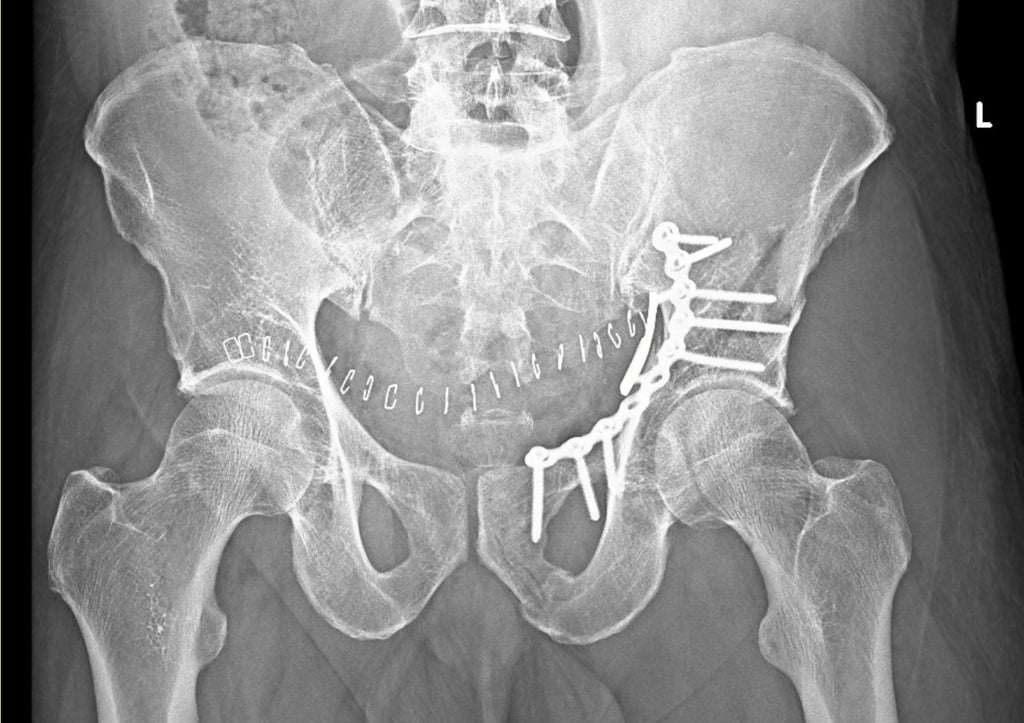

Surgical intervention is a critical component in the management of pelvi-acetabular fractures, as these injuries often lead to significant morbidity and complications if not addressed appropriately. The primary surgical technique utilized is open reduction and internal fixation (ORIF), which aims to restore anatomical alignment and stabilize the fracture. ORIF is indicated for specific fracture patterns, such as those involving displacement of the acetabulum or significant instability of the pelvic ring. This approach allows for early mobilization and enhances the prospect of functional recovery.

Another surgical option involves percutaneous fixation, which has gained popularity due to its minimally invasive nature. This technique is particularly advantageous in patients with soft tissue concerns or comorbidities that complicate traditional surgical approaches. Percutaneous fixation may not offer the same fine control over fracture alignment as ORIF, but it reduces the risk of complications associated with extensive soft tissue dissection.

The choice of surgical method is largely influenced by the type and severity of the fracture, the patient’s overall health, and the presence of any concurrent injuries. A thorough assessment and imaging studies help guide orthopedic surgeons in determining the most appropriate strategy. Potential advantages of surgical treatment include pain relief, restoration of joint function, and decreased risk of post-traumatic arthritis. Nonetheless, challenges such as the risk of infection, nonunion, and other complications must be considered when planning surgical treatment.